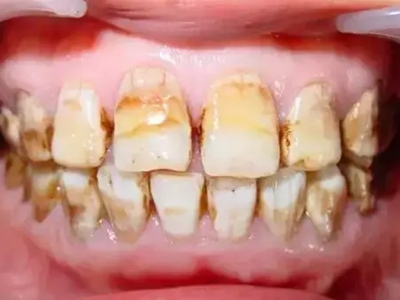

牙釉质发育不全牙齿棕色有缺损图

牙釉质发育不全患者牙齿出现明显的缺损表现,并于表面形成深褐色的蜂窝状、竖条状的凹坑,甚至形成洞,患者上下牙失去咬合能力。